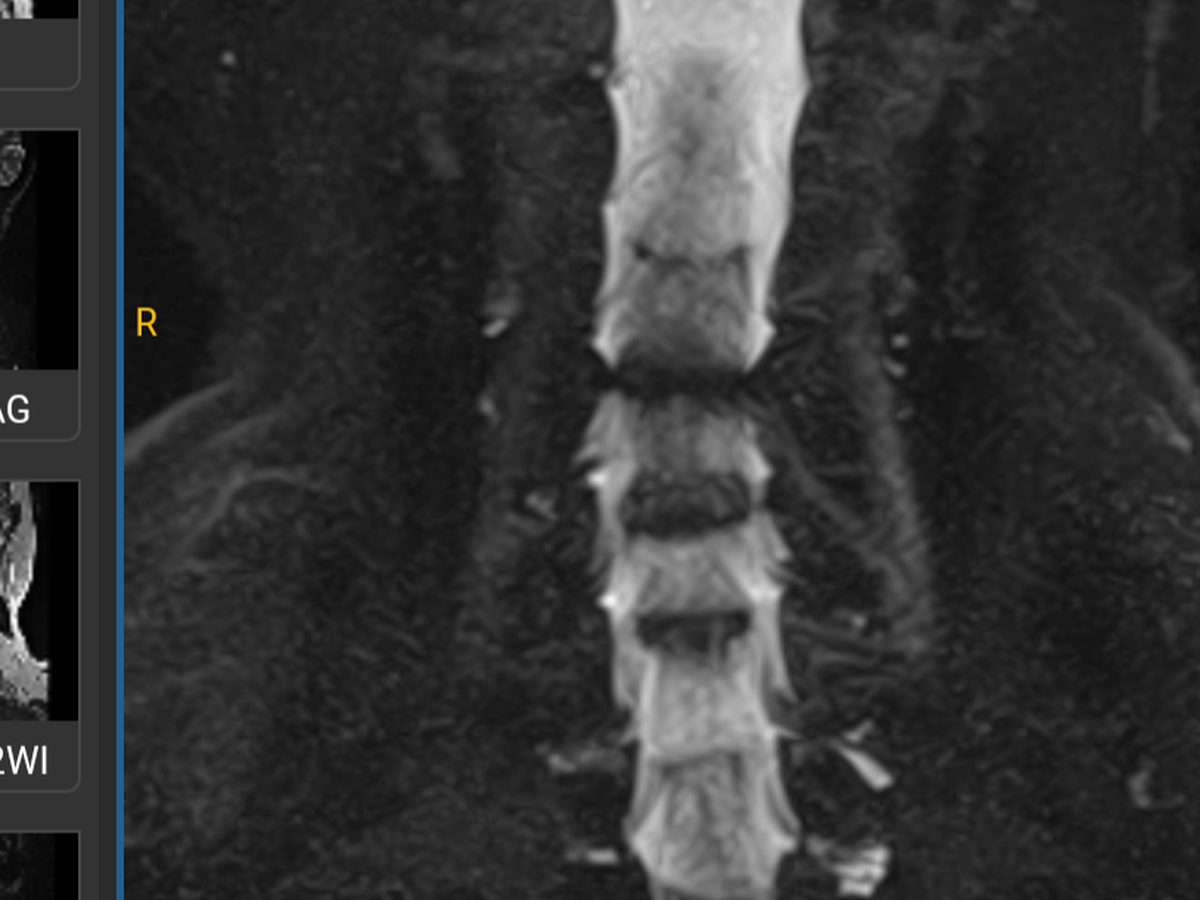

Hola me llamo Soledad de Jesús Tiburcio Cobos tengo 67 años, requiero una cirugía disectomia de columna cervical en las vértebras (C4-C5, C5-C6, C6-C7) y la colocación de cajas auto bloqueantes, de no recibir el tratamiento podría quedar cuadraplejica por lesión en médula, ayúdame a recobrar mi salud para poder seguir siendo independiente. Los fondos recaudados serán utilizados para cubrir los costos de hospitalización, intervención quirúrgica, medicamentos, rehabilitación de la misma.